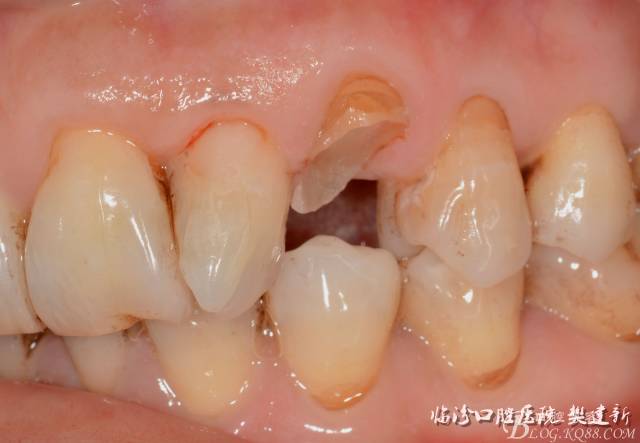

圖10  修復(fù)體代入口內(nèi)照

640 (9).jpg